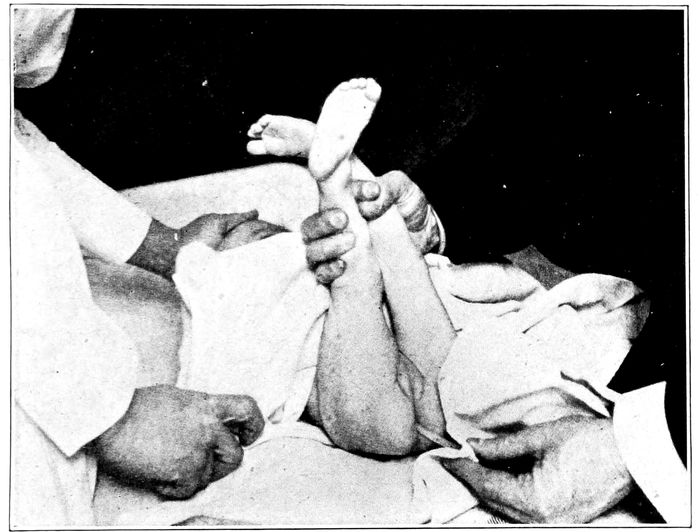

Byrd’s method of artificial respiration. Extension and inspiration |

280 |

| |

| 119. |